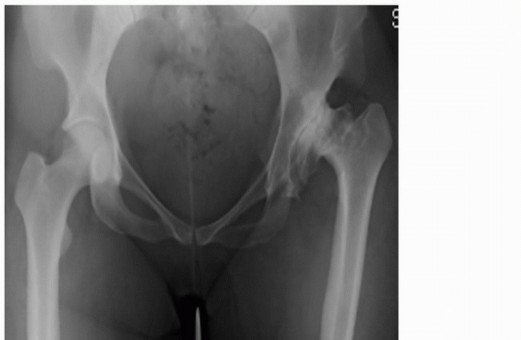

Head-Sparing Procedures for Osteonecrosis of the Femoral Head INDICATIONS/CONTRAINDICATIONS Osteonecrosis of …